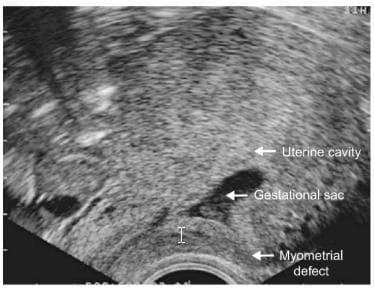

Pregnancies located below the internal os - cervical and Caesarean scar pregnancies

- Cervical pregnancy is defined as the implantation of the conceptus within the cervix, below the level of the internal os. Caesarean scar pregnancy is a novel entity, which refers to a pregnancy implanted into a deficient uterine scar fol-lowing previous lower segment Caesarean section [48].

- Prior to the introduction of high resolution transvaginal scanning, the distinction between cervical and Caesarean section scar pregnancies was not possible. In older litera-ture 33% of 'cervical' pregnancies occurred in women with a history of previous Caesarean section, which indicates that scar pregnancies probably account for a significant number of ectopics below the level of the internal os [49].

- The common characteristic of both cervical and Caesa-rean scar pregnancies is their implantation into myome-trial defects following previous intrauterine surgery . In case of cervical pregnancy the implantation

A clear anterior myometrial defect is evident after the removal of a Caesarean pregnancy.